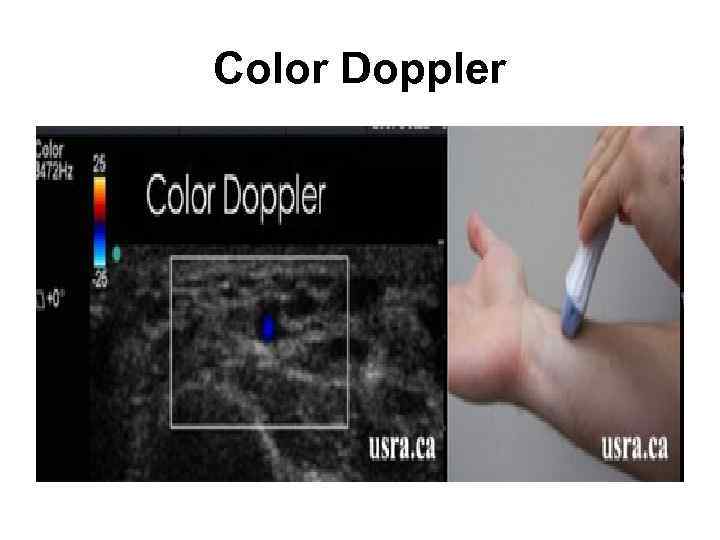

Цветовой допплер (Color Doppler)

Цветовой допплер (Color Doppler)

Color Doppler

Color Doppler

Цветовой допплер (Color Doppler) • выделение на эхограмме цветом (цветное картирование) характера кровотока в области интереса. • Кровоток к датчику принято картировать красным цветом, от датчика - синим цветом. • Турбулентный кровоток картируется сине-зеленожелтым цветом. • Цветовой допплер применяется для исследования кровотока в сосудах, в эхокардиографии.

Цветовой допплер (Color Doppler) • выделение на эхограмме цветом (цветное картирование) характера кровотока в области интереса. • Кровоток к датчику принято картировать красным цветом, от датчика - синим цветом. • Турбулентный кровоток картируется сине-зеленожелтым цветом. • Цветовой допплер применяется для исследования кровотока в сосудах, в эхокардиографии.

Цветовой допплер • Кровоток к датчику принято картировать красным цветом, • от датчика - синим цветом. • Турбулентный кровоток картируется сине-зелено-желтым цветом.

Цветовой допплер • Кровоток к датчику принято картировать красным цветом, • от датчика - синим цветом. • Турбулентный кровоток картируется сине-зелено-желтым цветом.